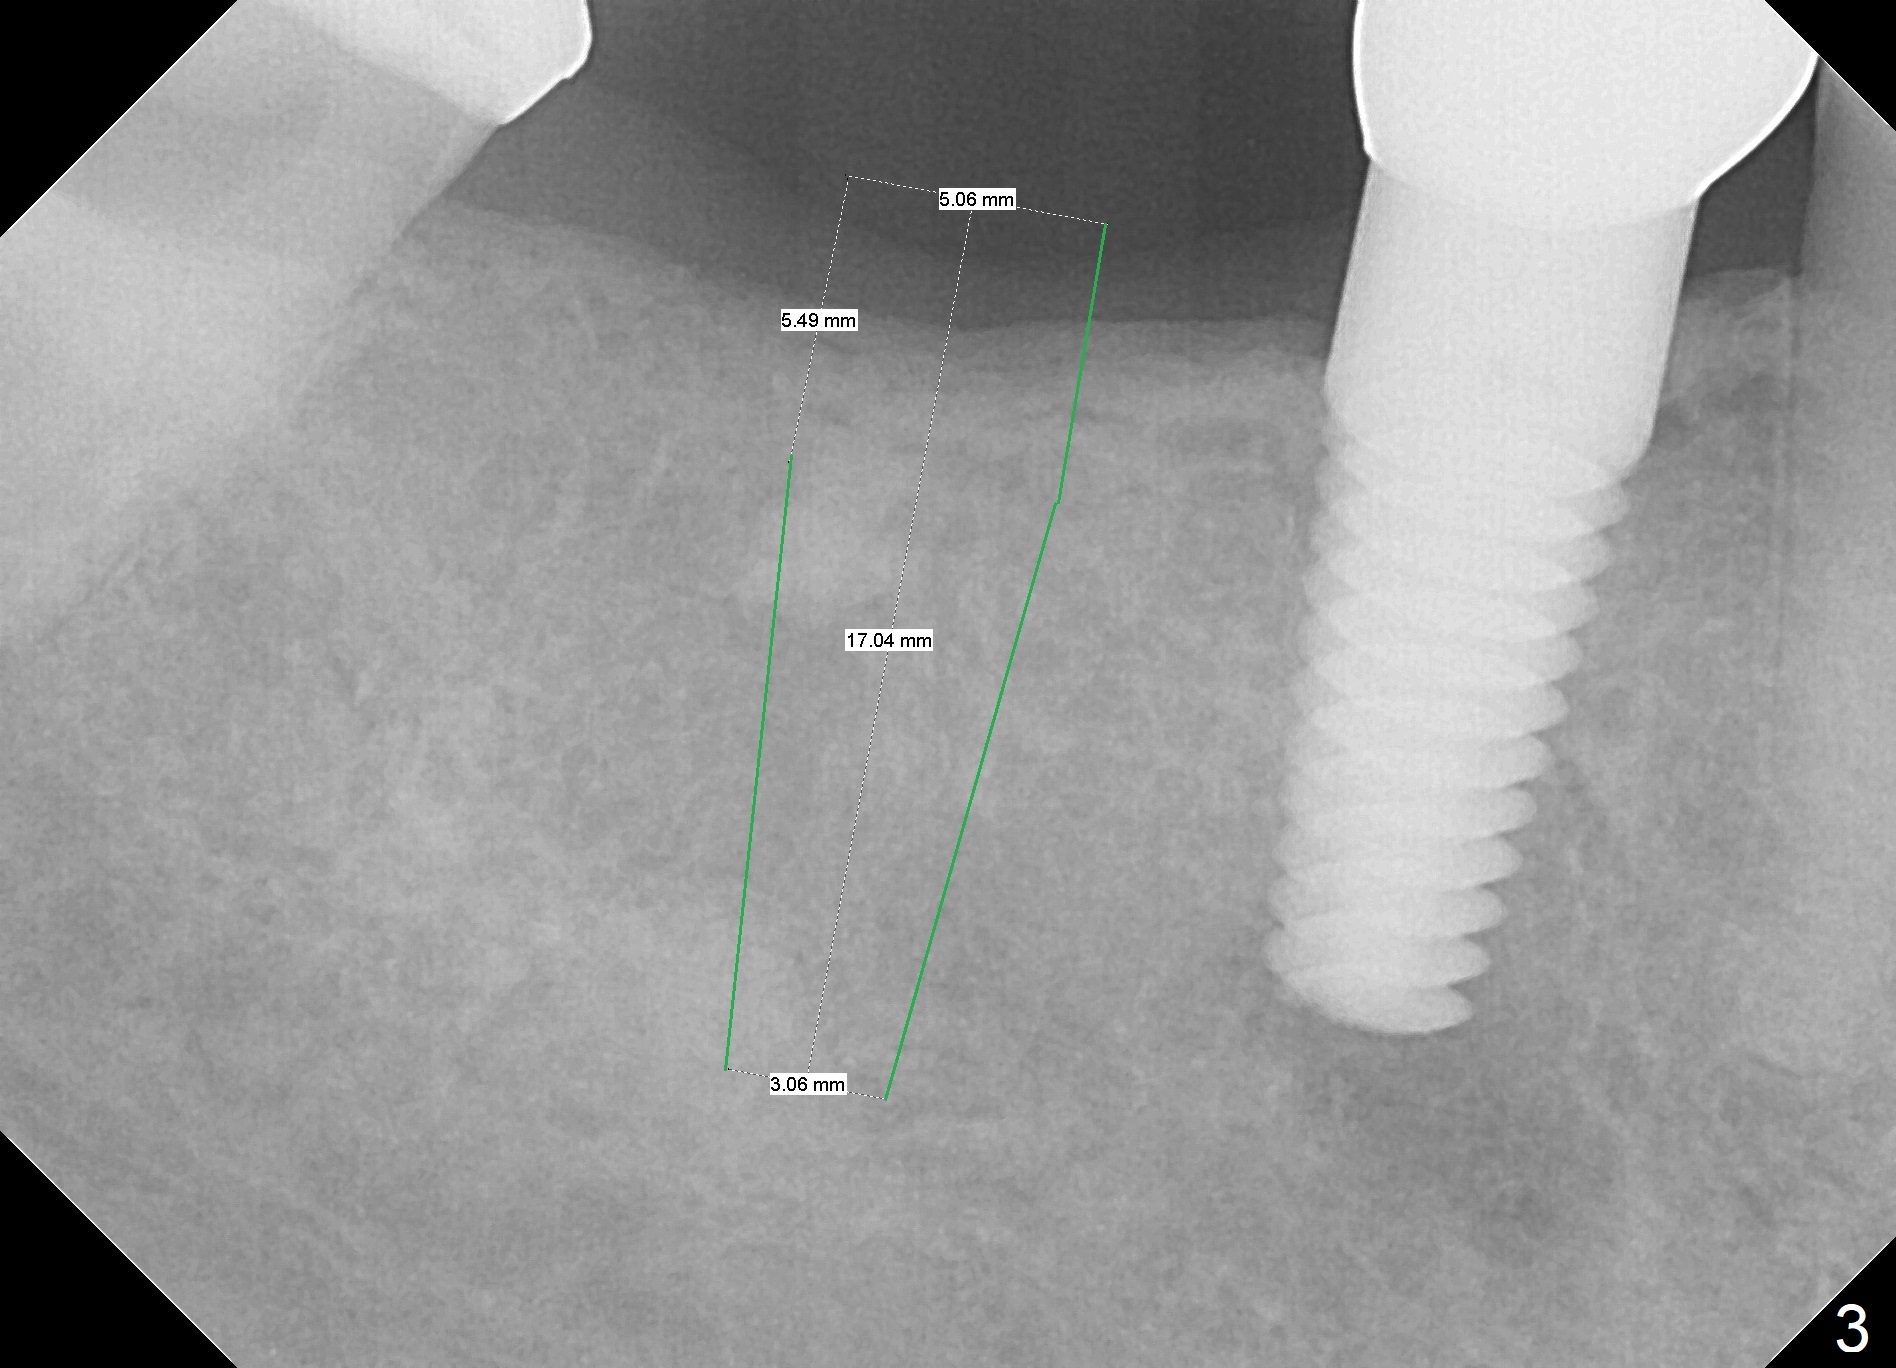

A 53-year-old woman returns for follow-up, requesting implant restoration at the sites of #30 and 31. The edentulous space is ~14 mm mesiodistally (Fig.1), whereas a 6x17 mm implant was placed at #19 with ~13 mm space (Fig.2). If the ridge at the LR molar region is wide enough buccolingually (3.5-5 mm Implant Positioners), place one implant (Fig.3, 4 mm Implant Spacer). Otherwise, two of them will be placed (Fig.4).